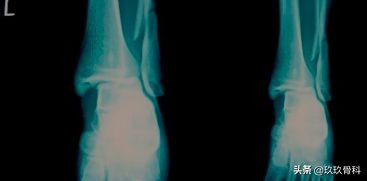

辅助检查

- X线 踝关节正侧位(必要时应加照踝穴位)

应力位片